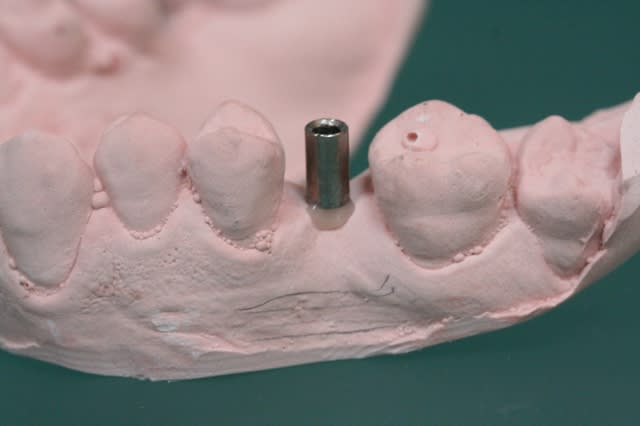

voyons maintenant un autre guide qui cette fois si utilise des canons de perçage en titane.

1 canon et empreinte

2 collage du canon avec du composite

3 attention à l'axe

4

5